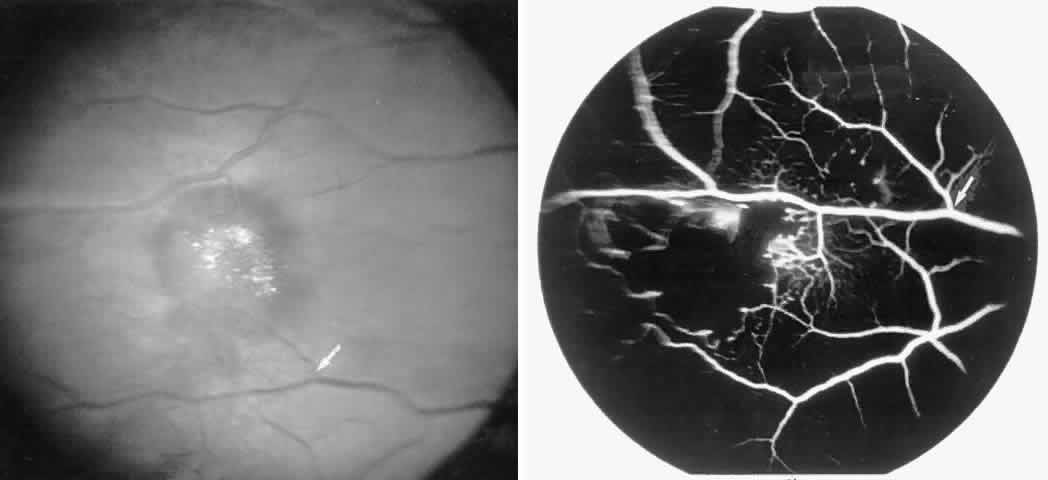

Choroidal Vascular Occlusions

Choroidal vascular occlusions may occur focally at the level of the choroidal precapillary arteriole or capillary bed (Elschnig's spots) or from posterior ciliary artery occlusion. Although focal precapillary arteriole occlusions have not been specifically identified with sickle cell disease, clinical and histopathologic evidence of spontaneous posterior ciliary artery occlusions have been reported in sickle cell disease.109,110 The findings are similar to those described following compression of the eye during general anesthesia and after heavy peripheral photocoagulation.111,112 In the acute phase, the occlusions appear as white, circumscribed, triangular patches at the level of the retinal pigment epithelium and outer retina. Over the following weeks, the white lesions fade and retinal pigment epithelial mottling develops (Fig. 15). Since patients with acute ciliary artery occlusions may be asymptomatic and the diagnosis is often based solely on the appearance of peripheral pigment mottling, the frequency of this complication remains uncertain.

Fig. 15. A 25-year-old man with homozygous sickle cell anemia and proliferative sickle retinopathy. A. Photograph demonstrating nonperfusion and wedge-shaped pigment mottling representing a choroidal infarction. B. Fluorescein angiogram demonstrating hyperfluorescence at the level of the retinal pigment epithelium.